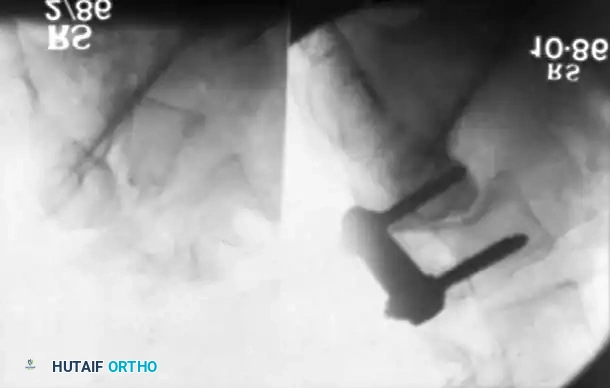

For lower lumbar and lumbosacral curves, an anterior transperitoneal or retroperitoneal approach is utilized.

As illustrated above, an anterior approach for the resection of the L4-L5 disc, the L5 vertebral body, and the L5-S1 disc can be achieved through a transverse incision across the rectus abdominis. The great vessels (aorta, inferior vena cava, and the iliac bifurcations) must be meticulously identified and mobilized laterally. The structural resection is performed directly between the bifurcation of the great vessels.

Following the anterior release and interbody grafting (often utilizing structural allograft or titanium cages packed with autograft/allograft), the patient is staged for the posterior procedure.

Stage 1 (Anterior): The L5 vertebral body and adjacent discs are completely excised via an anterior approach, decompressing the anterior neural elements and mobilizing the spine.